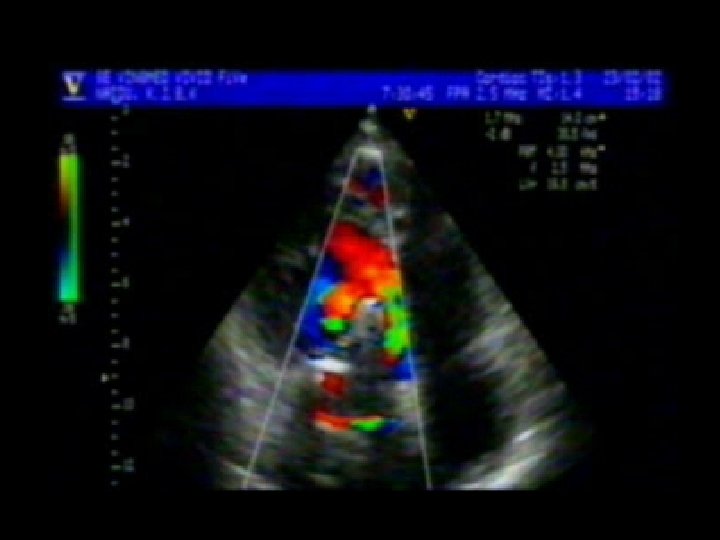

Nagi Reddy • • M 59 / Yrs AVR ; Tilting disc Pro. Mechanical Valve Severe Paravalvular AR Mod TR ; Mod severe PAH RVSP = 71 mm Hg